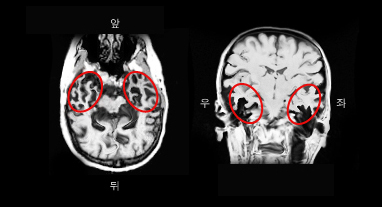

의미 치매 환자의 MRI. 측두엽의 위축이 두드러짐.

다른 치매와 마찬가지로 신경심리검사를 통하여 치매 여부를 판단하고, 그 아형을 분류한다. 또한 뇌 자기공명영상(뇌 MRI) 및 양성자단층촬영(PET) 등으로 다른 치매와 감별을 시도한다. 이마관자엽변성 환자의 MRI를 보면 이마관자엽치매(FTD)는 전두엽의 위축이 두드러지고, 의미치매는 측두엽의 위축, 그리고 진행성비유창성실어증은 브로카영역의 위축이 뚜렷하다.